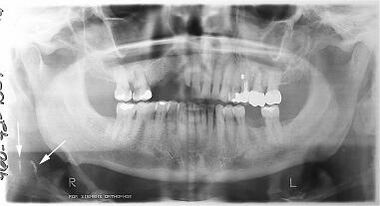

Ортопантомография (от греч.: orthos — прямой, правильный, pan — всё, tomos — ломоть, отрезанный кусок и grapho — писать, рисовать) — особый вид рентгеновской съёмки костей лицевого скелета, при котором они «развёртываются» в одну плоскость[1]. Другими словами рентгенологическое исследование в стоматологии, челюстно-лицевой хирургии, косметологии, позволяющее получать развёрнутое изображение всех зубов с челюстями, прилежащими отделами лицевого скелета. Является первичным рентгенологическим исследованием[2].

3. Костей челюстей и прилежащего лицевого скелета. Переломы (травматические, патологические) костей челюсти и лицевого скелета, новообразования, воспалительные процессы (остеомиелит, периостит), состояние полостей в костях (околоносовых пазух) и пр.

Галерея